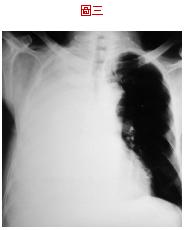

14. 有一男性病人,62歲,從某醫學中心轉來住院,主訴呼吸困難,帶來的報告是肋膜積液細胞學為腺癌,胸部X光如圖三,請問下列何種步驟為最優先? (A) 插入胸管引流,減輕症狀。 (B) 插入 pig tail 細管引流。 (C) 用針抽水,每天不超過1000毫升。 (D) 做超音波檢查,看看有無腫瘤。 (E) 做支氣管鏡檢查,看支氣管是否堵塞。